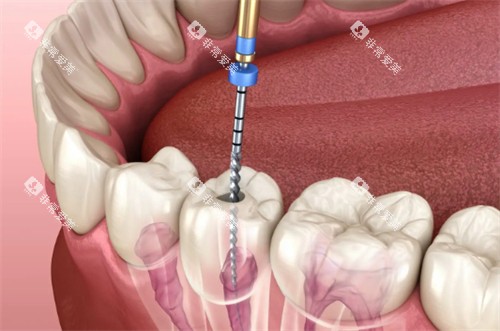

较高的医疗设备

该门诊部引进了一系列国内外较高的口腔医疗设备,如智能化口腔全景机、口腔 CT、激光治疗设备等。

这些设备能够为医生提供较准的诊断依据,提高治疗的比较准度和靠谱性。

以智能化口腔全景机为例,它可以快速、清晰地拍摄口腔全景图像,让医生齐全了解患者的口腔状况,为制定治疗方案提供有力支持。

同时,较高的设备也能减少患者的治疗时间和痛苦,提高治疗结果。